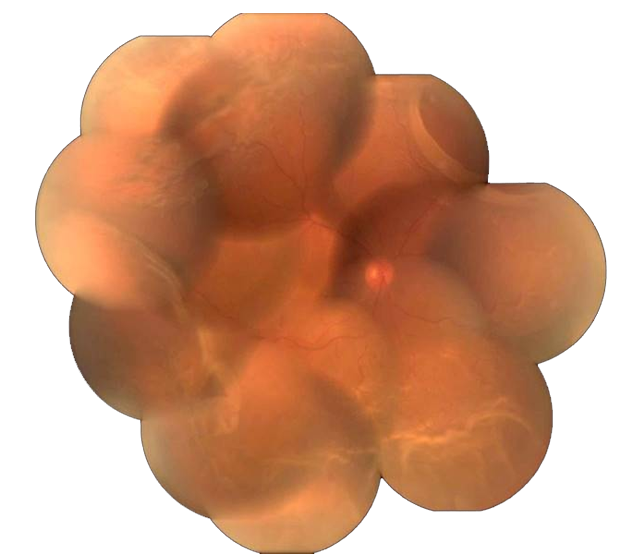

WET ARMD -: Also commonly known as CNVM, characterized by formation of new blood vessels at macula, which are very fragile and leak causing accumulation of blood at macula further leading to loss of vision.

Diagnosis :- Detailed fundus evaluation, OCT (Optical coherence tomography), FFA (fundus fluorescein angiography).

Treatment :–Intravitreal Antivegf agents.